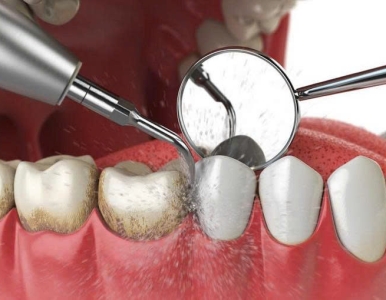

Bao lâu nên cạo vôi răng? Tìm hiểu tần suất lấy cao răng chuẩn giúp ngăn ngừa hôi miệng, viêm nướu và bảo vệ răng miệng hiệu quả.

Vôi răng là mảng bám cứng đầu gây hôi miệng, viêm nướu và mất thẩm mỹ. Tìm hiểu nguyên nhân, cách phòng ngừa và quy trình cạo vôi răng nhẹ nhàng, không đau tại Nha khoa SV – Quận 3.

Cạo vôi răng định kỳ giúp phòng ngừa viêm nướu, hôi miệng và giữ răng chắc khỏe. Tìm hiểu quy trình, lợi ích và chi phí cạo vôi răng tại Nha khoa SV – nha khoa uy tín Quận 3.